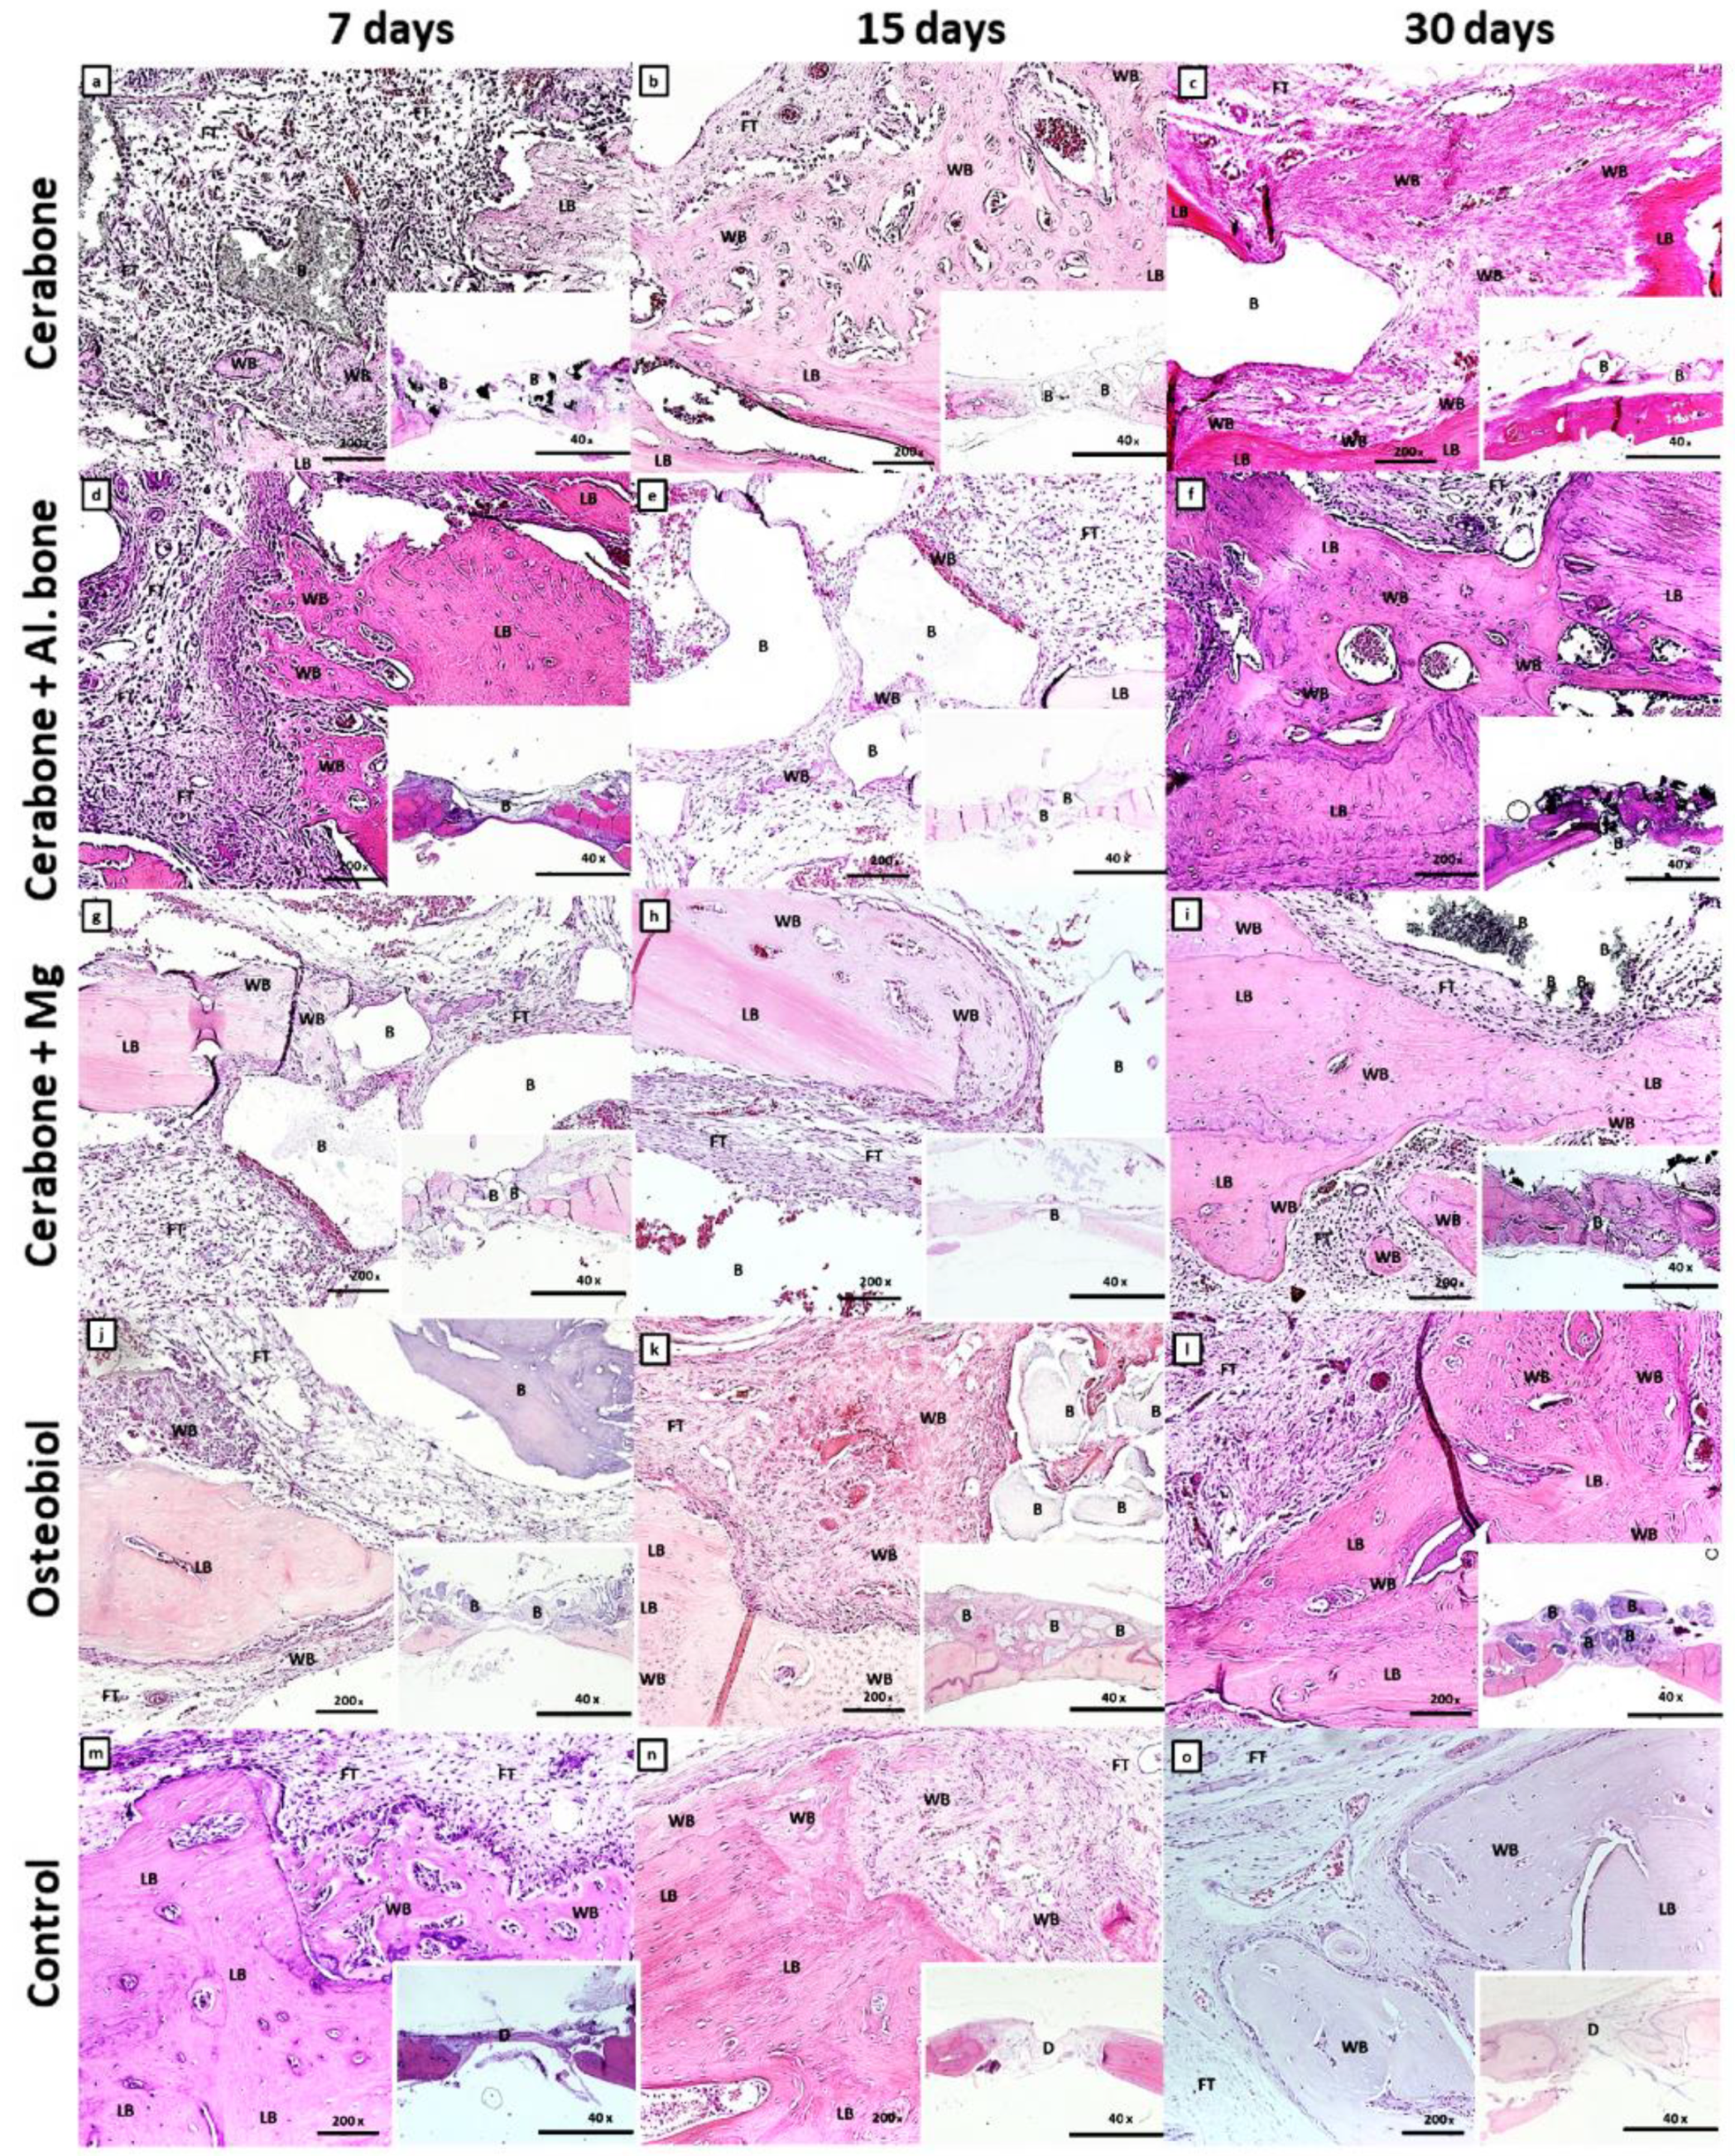

Figure 2 presents stages of bone defect healing, followed by days 7, 15, and 30.

On day 7 of the bone defect healing, ossification centers and islets of the woven bone were visible within the MSC cluster, and a more extensive new bone formation along the edges of the defect (Figure 2a,d,g,j,m). Additionally, the transition of MSC into pre-osteoblasts, which line the surfaces of the newly formed bone, was observed in Cerabone® + Al. bone and control groups (Figure 2d,m). Along with deposition of newly formed bone at the edges of the defect, a reactive accumulation of cells was observed, probably of an inflammatory character around the biomaterial particles of the Cerabone® + Mg (Figure 2g).

On day 15, bone defect healing continued, with a greater amount of the woven bone invaded by small blood vessels at defect edges of Cerabone® and Cerabone® + Mg (Figure 2b,h). Ossification of MSC to immature bone continued from the edges towards the center, which was abundant with blood vessels in the OsteoBiol® group (Figure 2k).

With the exception of control group, on day 30, newly formed bone bridged over bone defect of all groups of xenogeneic biomaterials, and while little residual biomaterial was visible in the Cerabone® groups, it remained in sufficient amounts in the OsteoBiol® group (Figure 2i).

Figure 2. Microphotographs of the coronal sections of rat calvarial bone defects with implanted biomaterials: Cerabone® (ac); Cerabone® + Al. bone (df); Cerabone® + Mg (gi); Osteobiol® (j–l), and control (mo). For each group of implanted biomaterial, three representative time points were chosen: 7 days (a,d,g,j,m), 15 days (b,e,h,k,n), and 30 days (c,f,i,l,o). In each tissue section, biomaterial (B), lamellar bone (LB), woven bone (WB), and fibrous tissue (FT) within calvarial defect (D) were marked (HE staining, magnification 200×, microphotography in the right lower corner, magnification 40×).